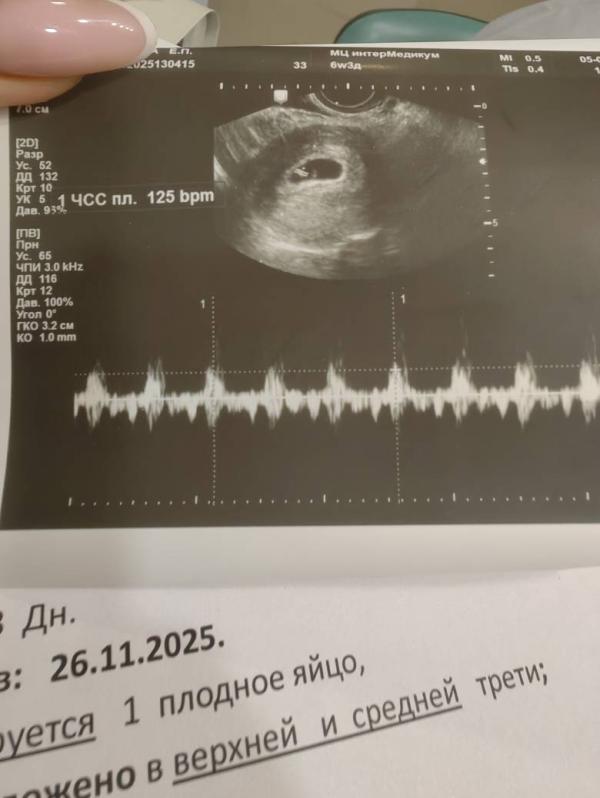

Услышать стук сердца малыша - бесценно! История о нашем первом колечке с бриллиантом.

Боже, как это прекрасно слышать стук сердца своего ребёнка ❤️